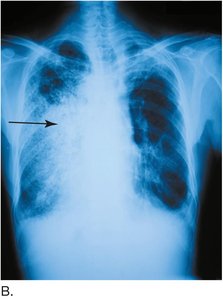

Chest radiography (CXR): X-ray imaging of the lungs

Diseases affecting the lungs include pneumonia, pulmonary edema, pulmonary embolism, tuberculosis, and cystic fibrosis. Pneumonia is an infection of the lung lobes, causing fluid and white blood cells to fill passages. Pulmonary embolism is a blockage of a pulmonary artery by an embolus.

Pneumonia: Bacterial, viral, aspiration, lobar, panlobar, pneumococcal, walking pneumonia

Tuberculosis: Caused by Mycobacterium tuberculosis, forms nodules in lungs